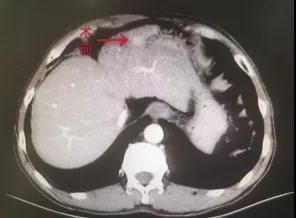

近日,陕西省中医医院血管病介入科成功开展首例原发性肝癌微波消融术。患者张某某,系原发性肝癌。入院检查,AFP:77.25ng/ml,上腹部增强CT示:肝左外叶见直径9mm小结节状异常强化影,考虑小结节型肝癌。

血管病介入科主任邓有峰立即组织科室成员进行病例讨论,在充分评估患者目前情况及手术风险后决定对患者行肝癌微波消融术。2020年12月02日在放射科积极配合下行CT引导下肝癌微波消融术。常规消毒铺巾、局部麻醉后,将微波消融穿刺针在术前体表定位处逐层插入肝脏肿瘤瘤体内,经过约10分钟70℃消融治疗再次行CT显示原肝脏肿瘤部位出现气化现象可见多个小空洞,周围呈磨玻璃样改变。手术过程顺利,患者无特殊不适。术后第二天复查血常规、肝功无明显异常,患者出院。